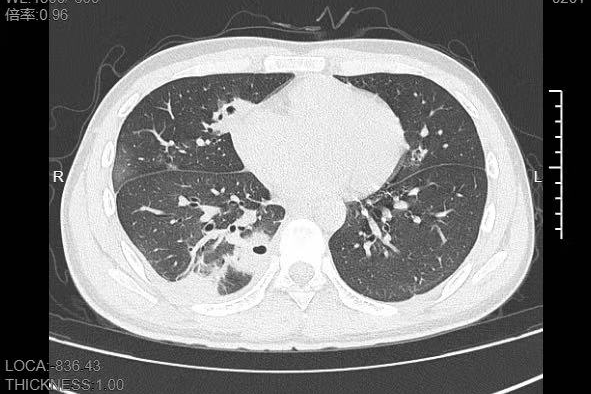

熬到第三天,小林已经烧到39℃,赶紧来到宁波大学附属第一医院就诊。接诊的呼吸与危重症医学科丁群力主任医师一看他的症状,立刻安排了CT检查。结果显示:小林的肺里有十几个空洞,部分肺组织已经坏死,这是典型的血源性肺脓肿。

图片